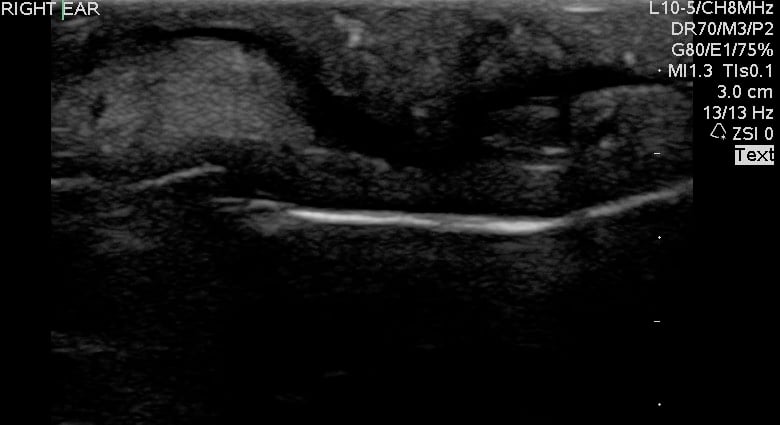

- Figure 1 and 2. Normal Ear

Video 1. Normal Ear - Anterior and posterior skin layers have thin hyperechoic appearance.

- Middle layer containing cartilage appears as a thin hypoechoic band.

- At the antihelix border the cartilage is thicker; the mean thickness is 0.8 ± 0.1 mm (at the middle third of the antihelix in transverse axis).

- At the lobule the mean thickness is 6.9 ± 1 mm.

- Normal Cartilage: